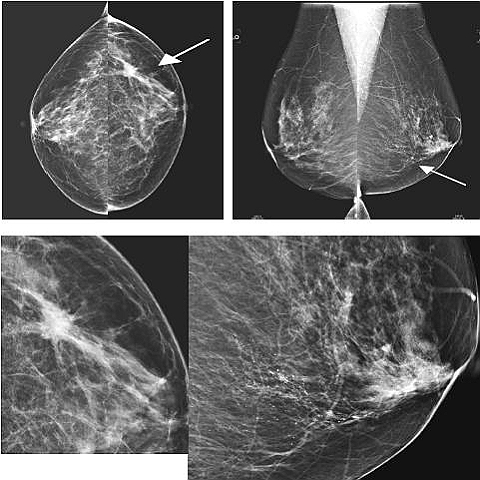

装置はいろいろな角度をつけることができます。標準の撮影では、上下方向(頭尾方向)と、台を斜めにして体に沿った角度をつけた斜め方向(内外斜位方向)との2方向が撮影されますが、50歳以上の乳がん検診などでは、斜め方向だけ撮影する場合もあります。

Q3:マンモグラフィでは乳がんはどのように写りますか?

乳がんは白っぽいかたまり“腫瘤”や、白い細かな顆粒“石灰化”などで見つけられます。乳腺が引きつれたようになっていたり、ゆがんだように写っているときも注意が必要です。

ただ、“がん”だけがそのように写るのではなく、良性の病気でも同じように写って見えるものもあります。マンモグラフィで二次検査が必要ですと言われても、全部が乳がんというわけではないので、いたずらにこわがらないで、さらに、超音波の検査や、MRI、CTなどで良悪性の鑑別をつけていくことが必要です。